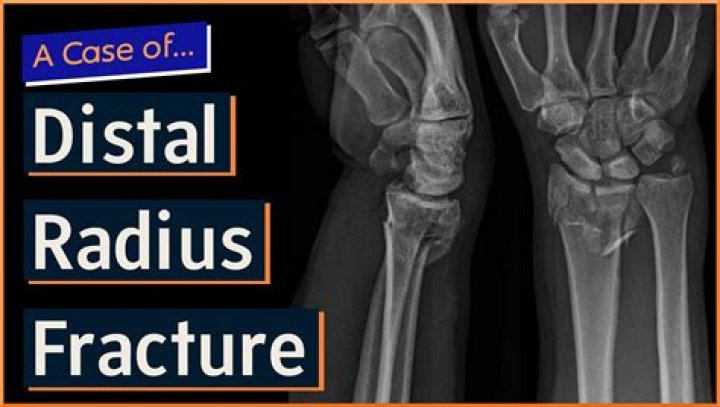

Distal radius fractures are one of the most common types of bone fractures. They occur at the end of the radius bone near the wrist. Depending on the angle of the break, distal radius fractures can be classified into two types: Colles or Smith. Falls are the main cause of distal radius fractures.

Therefore, the medical term for the most common type of "broken wrist" is a distal radius fracture (that is, the larger forearm bone is broken near the wrist). This kind of fracture is very common. In fact, the radius is the most commonly broken bone in the arm.

The most common type of fracture is a break of the radius bone, a long forearm bone. This is known as a distal radius fracture. when there is a break in the radius bone. A distal radius fracture occurs near the wrist joint on the thumb side, and it is typically the result of a fall onto an outstretched arm.